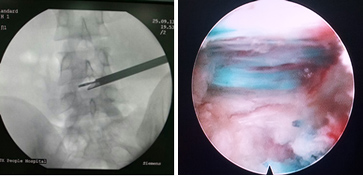

患者是一名19岁青年,因右下肢放射痛入院,疼痛的范围为大腿及小腿后外侧,入院前曾接受多方治疗,牵引、药物及其他理疗均未见效,疾病严重影响其生活及工作,基本只能卧床休息。MRI检查示L4/5椎间盘右侧巨大突出,压迫神经。对这类患者,手术指征明确,传统手术方式为腰椎后路L4/5开窗髓核摘除术,手术创伤大,术中需要剥离后方肌肉,手术时间长,出血量大,术后恢复慢而且有可能遗留腰痛症状。对于这样年轻的患者,可能会对其今后的生活造成一定的影响。经过充分的术前准备,陈钢主任为该患者在局麻下实施了椎间孔镜下椎间盘髓核摘除,通过在椎旁13CM处C臂机监视下穿刺,定位椎间盘及椎间孔位置,放入内窥镜,在直视下将椎间盘完全摘除。由于使用局麻,患者可以在术中和主刀交流,自诉症状缓解情况,该患者术中即感觉症状明显缓解,手术结束时,患者十分高兴,因为原来不敢活动的右腿活动自如了。该患者住院两天后即步行出院。与传统手术比较,因为没有剥离肌肉及切除椎板,手术切口只有1CM,大大减轻了患者的病痛及减少了常规住院的时间。

椎间孔镜技术是真正的微创技术,并被国际脊柱外科界所承认是一种损伤最小、适应症最广的椎间盘突出/脱垂的治疗技术, 是新的脊柱外科发展趋势和重要发展方向。其采用In Side--Out Side技术,通过安全三角区进入椎间盘,摘除病变髓核后退至椎间孔外,清除脱出的碎片;中央型突出,压迫椎管超过上关节突连线的病例,采用远外侧水平入路,直接摘除突出组织;游离型、黄韧带肥厚、钙化、椎管狭窄、神经孔狭窄等病例,采用椎间孔内入路,可摘除各种病变软组织、清理骨质;可以处理所有类型的椎间盘突出,还可以处理骨质,可做椎间盘复发的微创翻修手术(对于开放手术后复发的,MED手术后复发的),配合经皮固定技术可以完成退变疾病的治疗;椎间孔镜(是整体外径仅有6.3mm的同轴内窥镜,并配备有灯光、器械工作通道、注水及冲洗通道)仅需7mm的皮肤切口,从病人身体侧方、侧后方、后方,采用水平、倾斜、垂直的入路方式,通过椎间孔直达椎间盘突出部位,在椎间盘纤维环之外做手术,不伤及椎板及黄韧带,不影响脊柱稳定性,在内窥镜直视下可以清楚的看到突出的髓核、神经根、硬膜囊和增生的骨组织,然后使用各类专用的抓钳摘除突出组织、镜下去除骨质并配合射频电极进行盘内消融、术中止血及封堵破损纤维环。创伤小:皮肤切口仅7mm(如同一个黄豆粒大小),术中出血不到 5ml,术后仅缝1针(亦可不进行缝合处理),是同类手术中对病人创伤最小、效果最好的治疗腰椎间盘突出的终极微创手术。